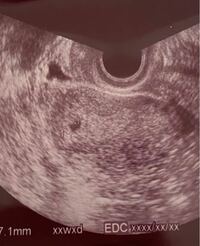

画像に卵黄嚢は見えていますか 本日5w6dで まだ心拍確認は出来ません Yahoo 知恵袋

胎嚢の上にある黒いのはなんですか 先生には何も言われなかったです 一 Yahoo 知恵袋